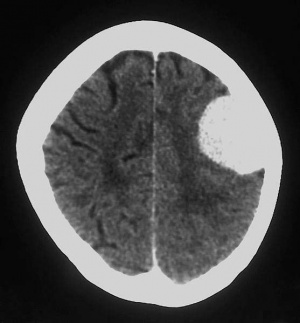

مننژیوم

مِنَنْژیوم (meningioma)

توموری که از پردههای مغز[۱] منشأ میگیرد. این تومور بهآهستگی رشد میکند و تقریباً همیشه خوشخیم است. چنانچه درمانی صورت نگیرد، در مغز باعث ناتوانی عصبی پیشرونده و گاه صرع[۲] میشود. چنانچه در نخاع پدید آید، منجر به فلج اندام تحتانی و ازدسترفتن حس[۳] در آنها میشود. اگر دسترسی به تومور آسان باشد، معمولاً آن را کاملاً خارج میکنند.